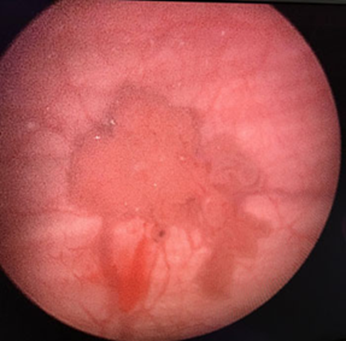

Endoscopic view of Bladder Tumor Before TURBT Surgery

Endoscopic view of Bladder Tumor After TURBT Surgery

Transurethral Resection of a Bladder Tumour (TURBT) –Cancerous bladder tissue is removed through the urethraSubsequently, chemotherapy or immunotherapy can be directly given inside the bladder through urinary catheter.